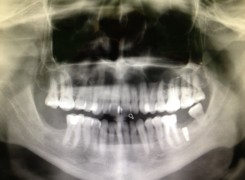

Pan Ryszard trafił do Naszego Gabinetu z jasno sprecyzowanym oczekiwaniem. Miał 84 lata i chciał odzyskać możliwość swobodnego spożywania posiłków oraz poprawienia sobie komfortu życia a także prosił aby przywrócić mu piękny uśmiech jakim cieszył się przed laty. Już na początku pierwszej rozmowy zastrzegł, że interesuje go wyłączenie rozwiązanie uzupełnieniem protetycznym stałym. Nie miał zamiaru użytkować żadnych protez ruchomych. Mając na uwadze powyższe wykonaliśmy Panu Ryszardowi zdjęcie pantomograficzne oraz badanie tomograficzne szczęki i żuchwy na postawie których zapanowywaliśmy Pacjentowi optymalne rozwiązanie – stałe uzupełnienie protetyczne w postaci 28 koron cyrkonowych zamontowanych do dwóch belek cyrkonowych które będą przymocowane do 16 implantów w konfiguracji 8 wszczepów w szczęcie 8 w żuchwie. Po omówieniu powyższego planu przystąpiliśmy do Wspólnej pracy której efekty w poszczególnych etapach prezentujemy poniżej.